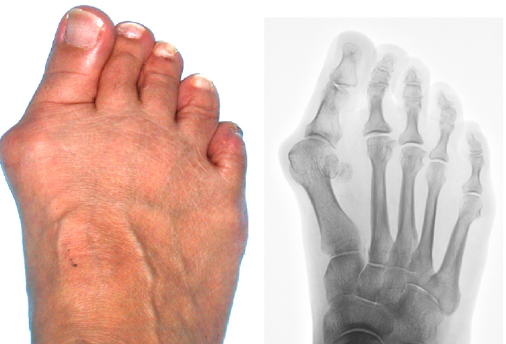

무지외반증("hallux valgus”)이란?

무지외반증은 발가락 통증을 일으킬 수 있는 특정한 상태입니다. 이는 발가락으로 통증을 유발할 수 있는 신경 주위의 조직이 두껍고 확장되는 경우 발생합니다. 이는 특히 세 번째와 네 번째 발가락 사이의 발의 앞부분에서 심한 불편함을 초래할 수 있습니다.

무지외반증의 증상

무지외반증의 흔한 증상은 다음과 같습니다.

- 발 앞부분에서 날카로운, 화끈한 통증.

- 영향을 받는 발가락에서의 저림 또는 따끔거림.

- 신발 안에 돌 또는 물체가 있다는 느낌.

발가락 통증의 원인을 파악하기 위해 의료 전문가는 X-선, 초음파 또는 MRI 검사를 포함한 다양한 진단 검사를 수행할 수 있습니다.